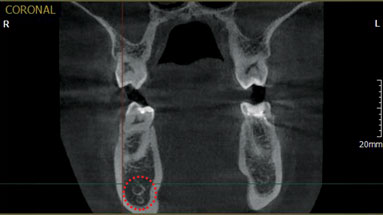

Программный продукт также имеет ряд преимуществ при анализе проделанной работы. Вся информация архивируется, в том числе возможно внесение различных фото после проведения эстетического лечения. Требования пациентов к итогам лечения зависят от их восприятия трудностей в полости рта, однако часто это только частично отражает истинную клиническую ситуацию. Многие пациенты получают информацию из изданий или бытовых советов знакомых. В большинстве случаев, они имеют весьма относительное представление о реальных особенностях этой процедуры, сложностях ее проведения и возможных в дальнейшем проблемах. Другие могут получить большой объем информации через интернет, но не могут упорядочить ее, или то, что они узнали, совершенно не подходит для их ситуации. Поэтому в задачи стоматологов входит убедиться, что пациент понимает суть своего состояния, возможности лечения, а также оказать ему помощь в выборе правильного решения. В этой связи приложение оснащено 200 мультимедийными роликами для создания комфортных условий консультаций пациентов, где в доступной форме отражена планируемая процедура вмешательства. Показательность информации, наряду с комментариями профессионала приводят к сотрудничеству пациентов для точного понимания своего клинического случая. Программное средство Ez3D-i V4, рассчитанное на работу с трехпроекционным объектом исследования по праву является передовым на рынке диагностической инженерии. При подготовке к хирургическому этапу имплантации программное обеспечение Ez3D-i V4 дает огромный спектр опций. Построение трех проекций, с возможностями переориентации осей, с точным измерением габаритов интересующей области, маркировки хода нижнечелюстного канала, в том числе, и, на кросс-секционном изображении (Рис.5), а также диагностика дополнительных ответвлений (добавочные каналы Робинзона)(Рис.6), визуализация верхнечелюстных пазух, виртуальный позиционер имплантатов (Рис.7), позволяющий спрогнозировать оперативное вмешательство с помощью любой фирмы - производителя имплантационных систем, измерение плотности костной ткани в зоне планируемой имплантации по шкале Хаунсфилда HU (Рис.8). Виртуальная реальность представлена в масштабе 1:1, что дает 100% информативности, а значит и 100% эффективности планируемого лечения. После того как программа произвела инсталляцию имплантата, хирург в приложении моделирует его ангуляцию, инклинацию и погружение, учитывая все анатомические факторы риска. Функции "Удалить или Скрыть" имплантат, используют при замене длины и диаметра имплантата или выборе иной марки производителя.

Рис.5 Выделение нижнечелюстного канала в П/О Ez3D-i V4

Рис.6 Дентальная объемная томограмма во фронтальной проекции. Раздвоенность нижнечелюстного канала в теле челюсти